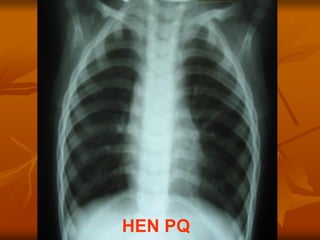

HEN PQ

3 / Chẩn đoán phân biệt:

 Hen

KHÒ KHÈ:

 Phải được bác sĩ xác nhận

PHÂN BIỆT

HEN NHŨ NHI & VTPQ

VẤN ĐỀ THỰC TẾ

PHÂN BIỆT HEN & VTPQ

HEN VTPQ

Khò khè tái phát Có (đặc trưng) ≤ 2 lần: 70%

Khởi phát của

khò khè

Cấp tính nếu do dị ứng

hay gắng sức

Từ từ

VHHTđồng thời Có: nếu nhiễm khuẩn Có

BHDƯ đồng thời Có: nếu hen dị ứng Thường không có

TSGĐ dị ứng/ hen Thường có Thường không có

Đáp ứng với

thuốc DPQ

Có (Đặc trưng) Không,

hay 1 phần

TCYTTG

 Cơn khò khè đầu tiên ở trẻ < 6 tháng

tuổi: hàng đầu là VTPQ.

 Cơn khò khè đầu tiên ở trẻ > 18

tháng tuổi: hàng đầu là hen.

CHẨN ĐÓAN PHÂN BIỆT

 Có thể khó  phân biệt rõ ràng ngay từ

đầu

 Xử trí ban đầu có thể tương tự nhau

 Tùy diễn tiến LS, CLS, XQ, đáp ứng ĐT

để  xác định

Hen nhũ nhi

Viêm tiểu phế quản